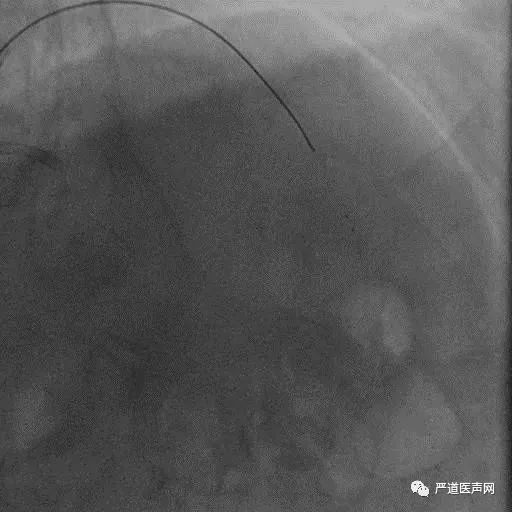

Case 1: Male 66 yrs, first attempt failed in local hospital

7F EBU 3.5, 6F SAL 1.0

• Stump

• Lesion length > 20 mm

• Absence calcification

• Promising landing zone

• Tortuosity epicardial CC

XT R KDL Parallel wiring UB3

Corsair Not Crossboss!

Stingray LP

Stick with GAIA Third

Final Results